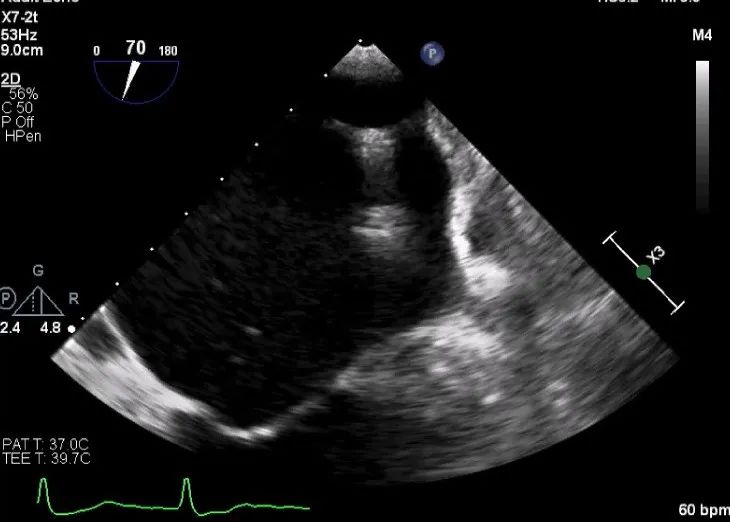

确定房间隔穿刺点:靠后

2D视图下测量大鞘长度2cm

3D视图打开夹子